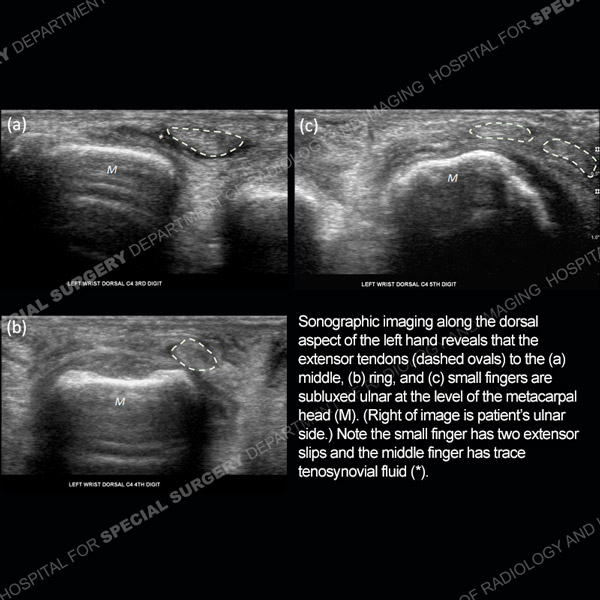

Featured Ultrasound of the Month CaseCase 186: 64-year-old woman with new left ring finger soft tissue swelling. |